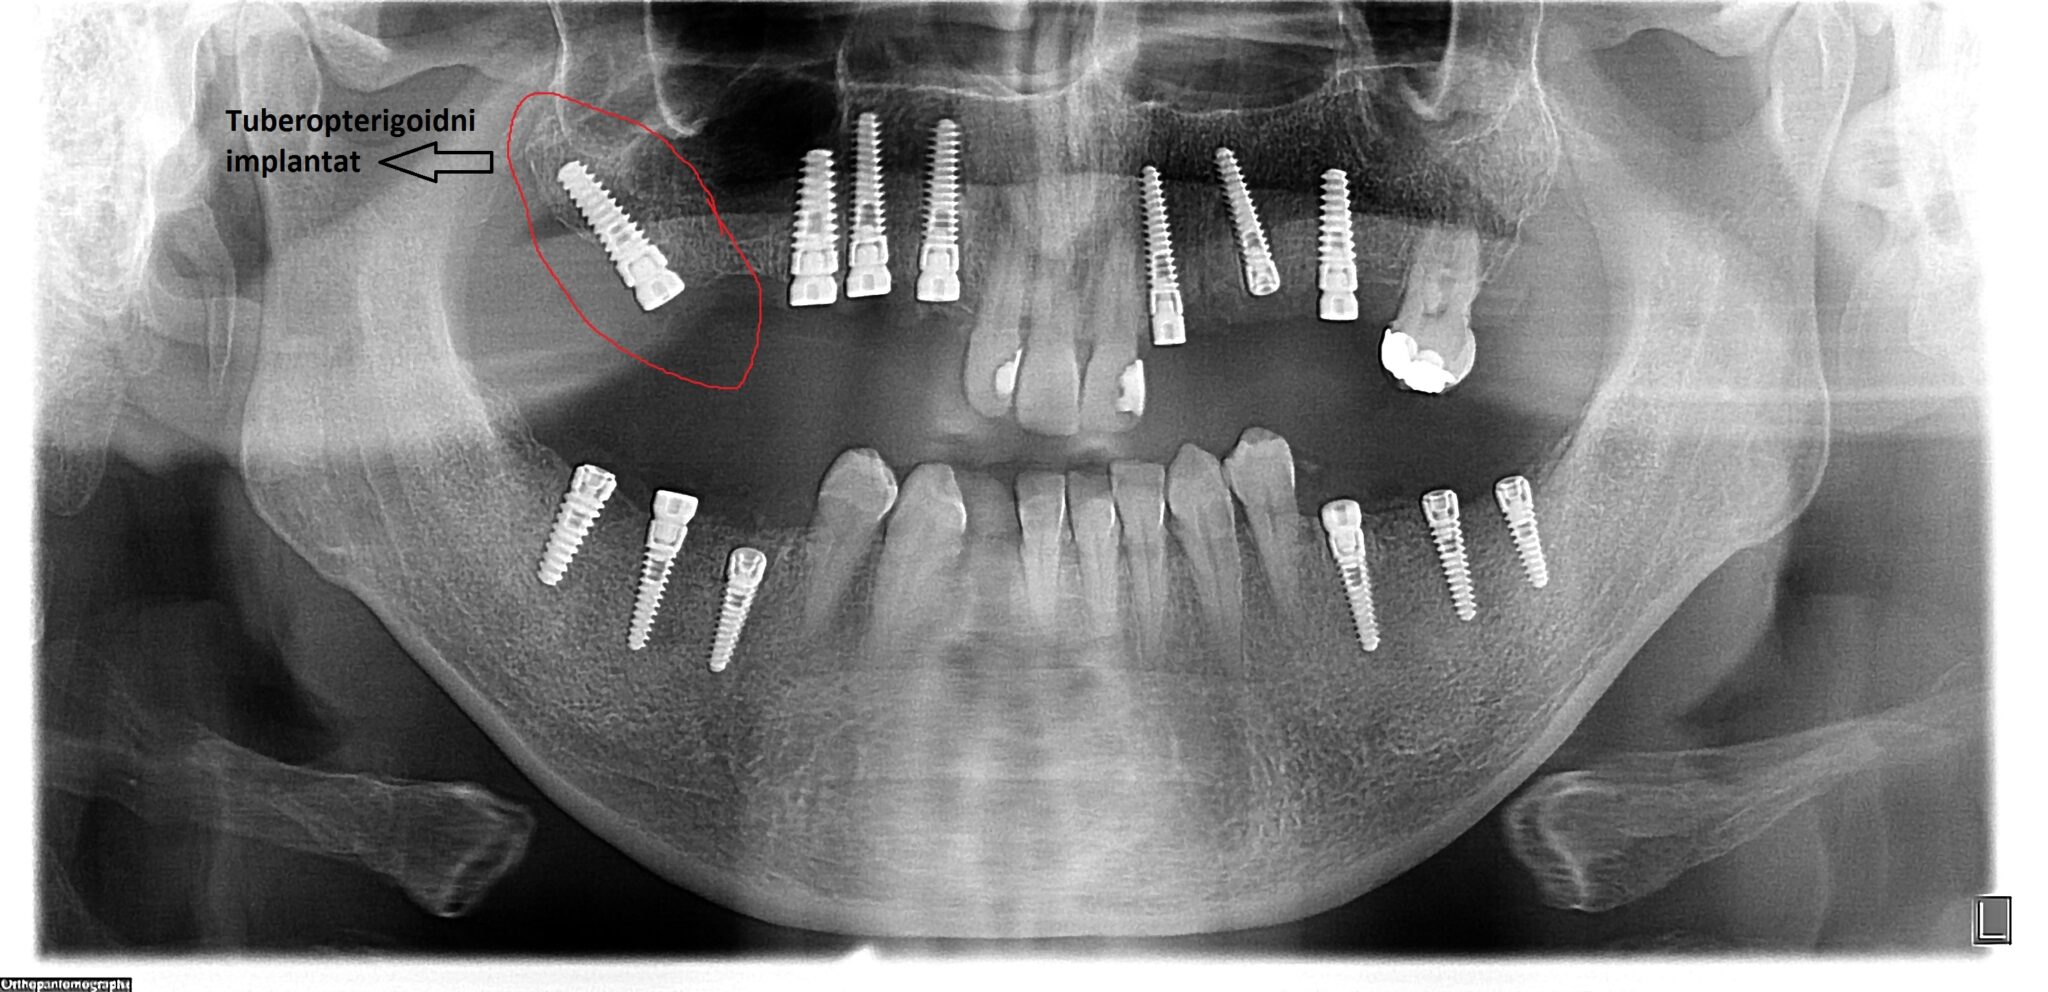

Na slikama su prikzani tubero-pterigoidni implantati postavljeni u cilju da se izbegne sinus lift procedura, čime je omogućena izrada fiksnog protetskog rada, sa kompletanim zubnim nizom, uz minimalnu površinu naleganja na meka tkiva.

Ovaj tip implantata omogućava izbegavanje sinus lift operacije, koja se inače koristi za povećanje koštane mase u predelu maksilarnog sinusa.

Operacija sinus lifta zahteva komplikovanu hiruršku proceduru, a dužina čekanja na definitivni protetski rad na implantatima u toj regiji traje i do dve godine. Ugradnja tuber-pterigoidnih implantata predstavlja relativno jednostavnu metodu, ali zahteva veliko iskustvo, preciznost i temeljno znanje iz anatomije i oralne hirurgije.

Tuber-pterigoidni implantat skraćuje vreme izrade definitivnog rada na implantatima i njime se izbegavaju neprijatnosti posthirurškog toka operacije sinus lifta.